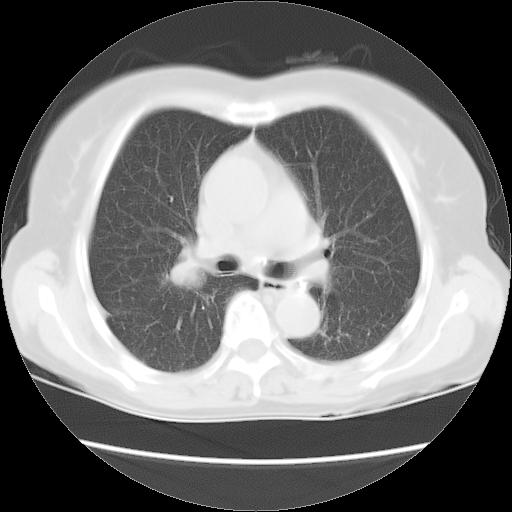

以下是引用夏季在2007-9-18 11:00:00的发言:[br]1。右肺肿块,周围有短毛刺,肺门侧有血管与其相连,胸壁侧有胸膜凹陷征,考虑周围性肺癌 2。左侧甲状腺软组织肿块,内有高密度钙化灶,考虑左侧甲状腺腺瘤。

以下是引用卜一在2007-9-18 14:41:00的发言:[br]右肺肿块:毛刺+胸膜凹陷征+供血血管+浅分叶+强化。支持:周围性肺癌 !另:左侧甲状腺腺瘤!